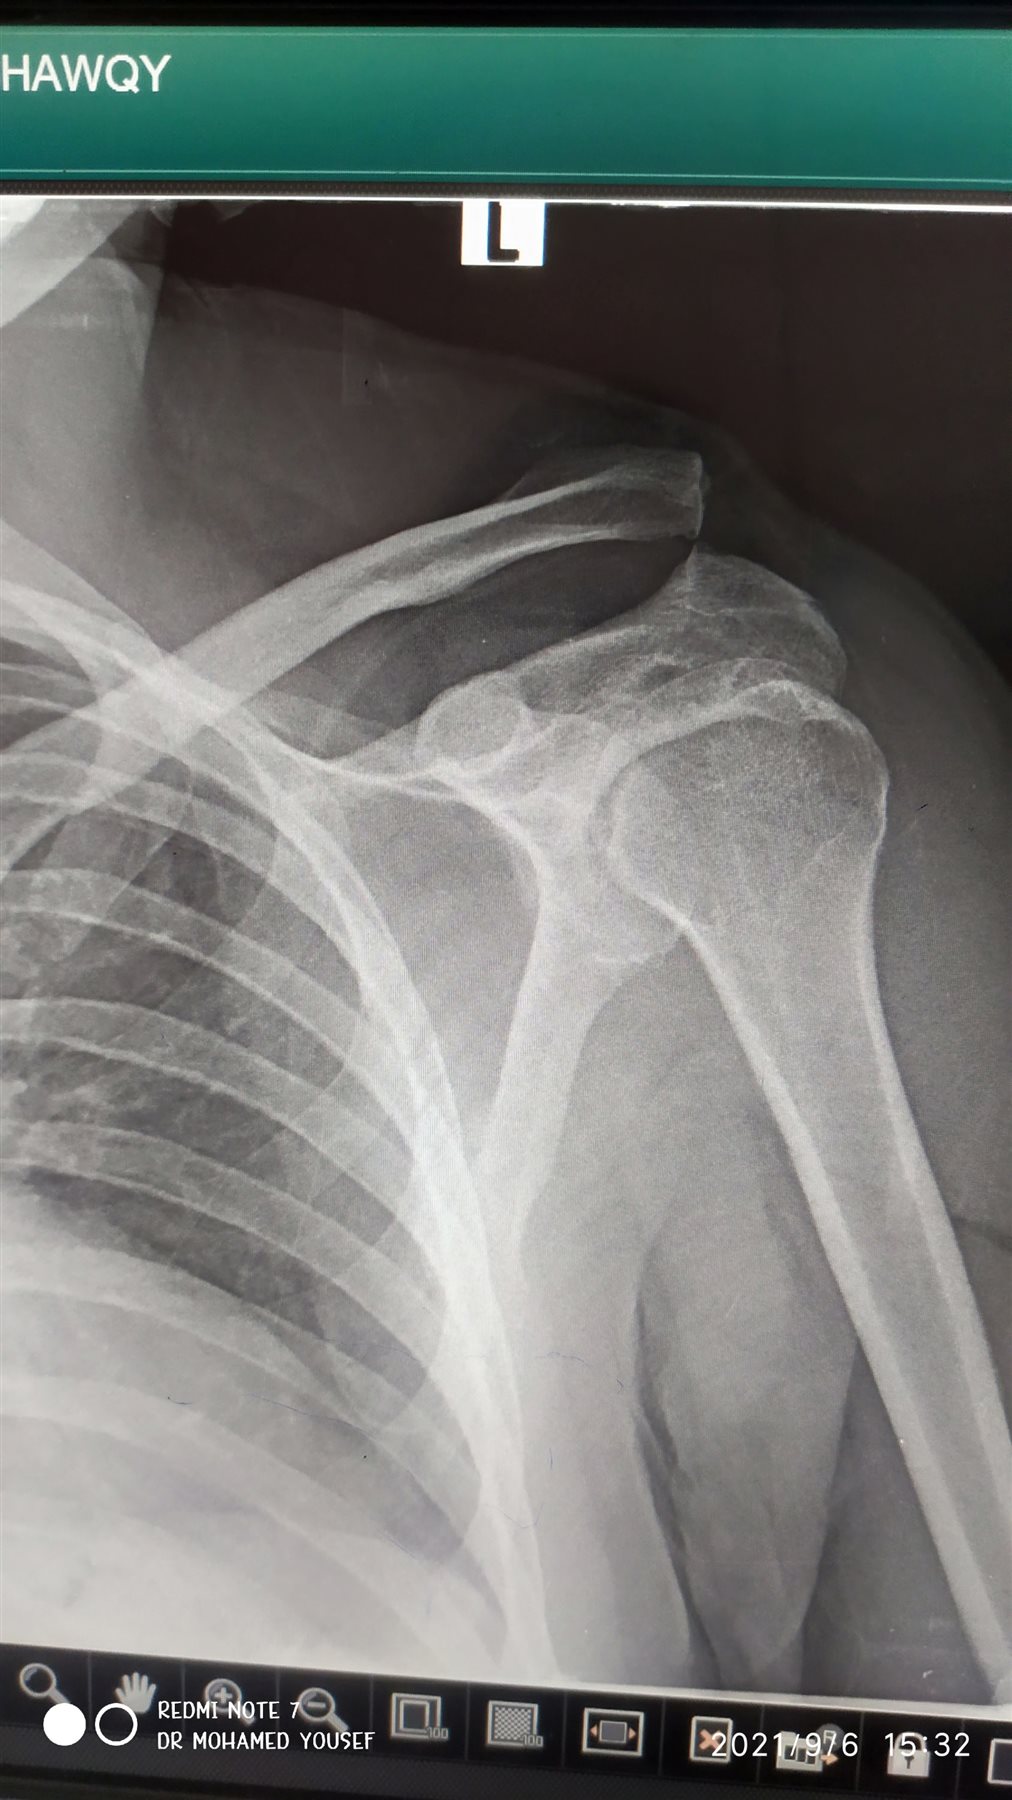

نجاح أول جراحة تثبيت خلع بمفصل الكتف في الدقهلية |صور

أعلن الدكتور سعد مكي، وكيل وزارة الصحة بالدقهلية، نجاح فريق طبي في إجراء أول عملية تثبيت خلع بمفصل الكتف، باستخدام تقنية جديدة بمستشفى دكرنس العام لمريض يبلغ من العمر 40 عامًا.

وأوضح وكيل وزارة الصحة، أن التقنية الجديدة تقلل من آلام ما بعد الجراحة لدى المريض، وتحقق التعافي السريع، كما أنها أفضل من الناحية التجميلية، ولا تستدعي إجراء عملية أخرى لإزالة الشرائح والمسامير المعدنية.